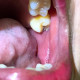

Izin menanyakan kasus yang dialami salah satu rekan sejawat yang praktik di Kalimantan. Pasien datang dengan kondisi mukosa bukal bilateral kemerahan, pipi terasa lebih tebal, sudah 3 hari, badan terasa gatal jika malam, tidak ada riwayat hipertensi dan diabetes. Lidah terdapat coating putih. Kalau makan makanan pedas atau panas tidak terasa perih. Tidak ada demam penyerta. Tidak habis mengonsumsi obat tertentu. KGB kenyal, mukosa kenyal dan menebal. Tidak meggunakan gigi tiruan.

Kalo dilihat dari foto klinisnya spertinya Oral Lichen Planus tipe Erosive.

Ciri khas OLP adalah lesi nya terjadi bilateral dan terdapat wickham's striae (papula putih memanjang dan bersilangan menyerupai jaring-jaring). Pada foto tersebut terlihat wickham's striae meskipun samar. OLP ini adalah kondisi autoimun yang etiologi paling sering adalah faktor psikis (kecemasan). Kondisi tersebut akan mengalami rekuren apabila terpapar kondisi berulang yang menyebabkan kecemasan.